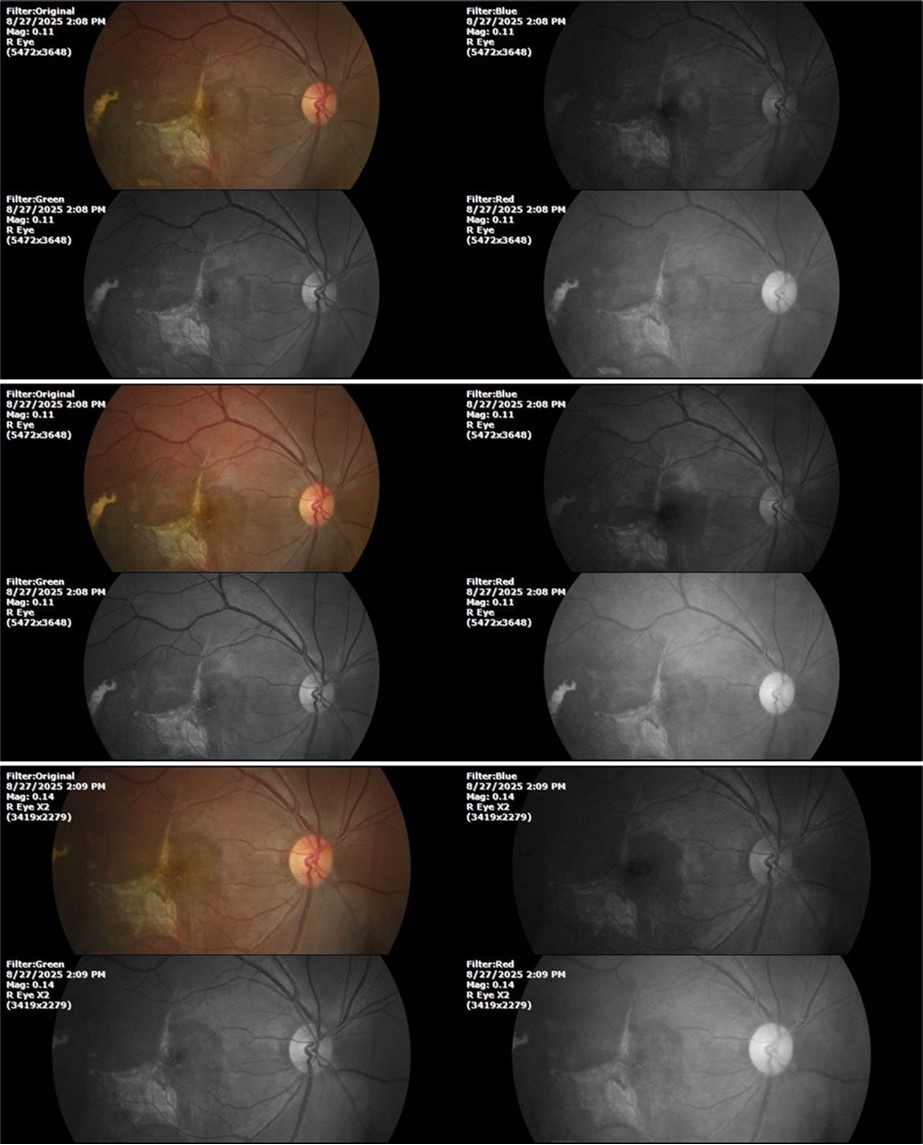

Figure 27.The three previous photographs of the right fundus show that the whitish mass composed mainly of phantom cells continues to decrease.

It's been fine, there's only a little veil that prevents it from seeing well completely, although it's very transparent (Figure 31, Figure 32, Figure 33, Figure 34, Figure 35, Figure 36).

Figure 33.The 3 previous photographs show that whitish mass has almost completely disappeared, and to date only a remnant remains on the left side of the photograph. The chorioretinal scar that is now observed corresponds to the area affected by the blunt trauma, which presumably caused rupture of Bruch's membrane. Fortunately, the macular region has recovered almost in its entirety, so the impairment in central vision was minimal.

Despite being a patient affected in the macular region by the blunt trauma he suffered at work, the recovery was very satisfactory, which is not easy to achieve with established orthodox treatments, including surgery and powerful anti- inflammatories.